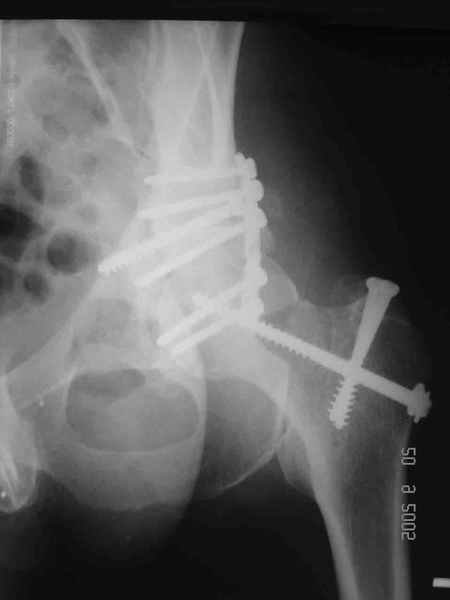

Уважаемые коллеги. Больной был оперирован в одну сессию 25 августа. Сначала на голень наложен спице-стержнвой аппарат. Затем выполнен остеосинтез вертлужной впадины Y-образным доступом. Пришлось дополнительно отсекать вертел. Шейка синтезирована спонгиозными винтами и спицами, вертел - спицами и стягивающей петлей. После операции находился на вытяжении 3 нед. Раны зажили первичным натяжением. Сейчас уже дома. Будет и дальше без нагрузки на левую ногу. Будем наблюдать в динамике. Ждем комментарии.

Перелом шейки был многооскольчатйй очень медиальный, по сути шейку и вертел расколотило об подвздошную кость с кучей мелких фрагментов, вертел был полностьб вовлечен в перелом, головка заподлицо скрывалась в расширенной вертлужной впадине. Качество кости приличное. Остатки дуги Адамса с предварительно проведенными винтами я вколотил в головку и компрессировал винтами - оказалось прочно, но образовался дефект верхнего отдела шейки, который был заплнен фрагментами фиксироваными трансфрактурными спицами - отсюда пучек.

Вертел во время доступа пришлось еще рубить, т.к.

переломы распространялись чересчур дистально.

Отсюда еще пучек спиц.